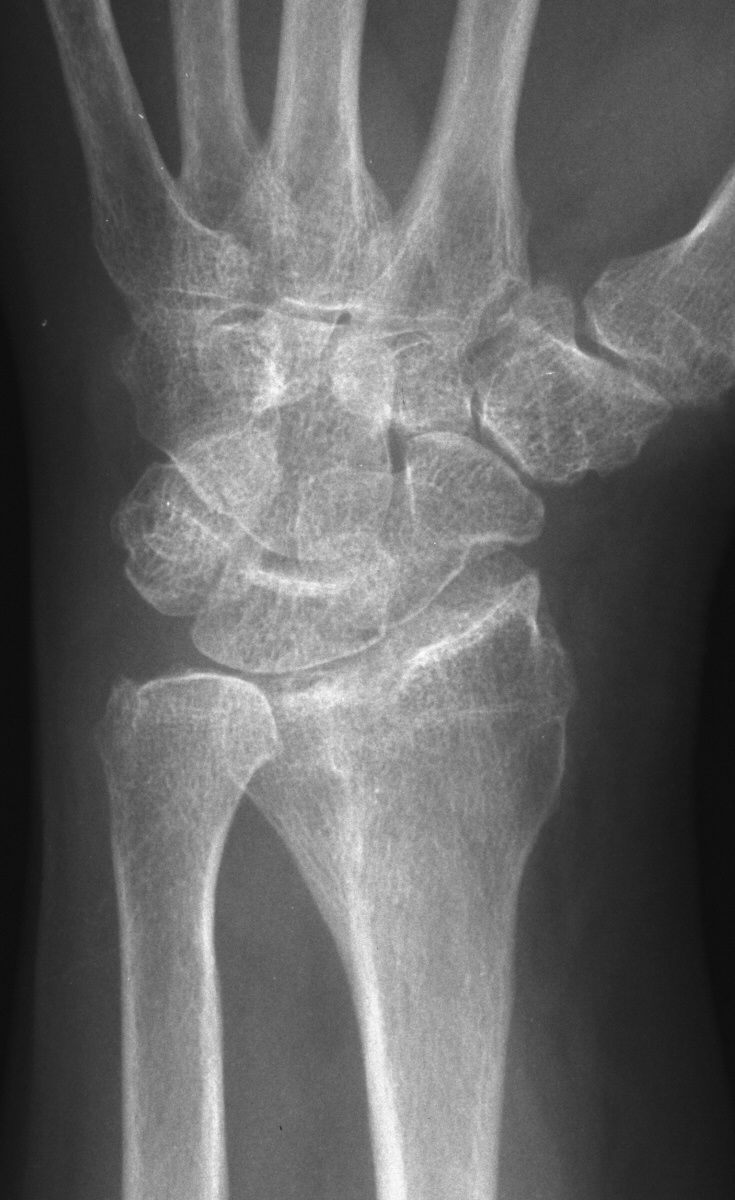

| This patient presented with

persistent wrist pain, swelling and stiffness one year out from closed

reduction and external fixation of a n intraarticular distal radius

fracture. |

| No prior films were

available. Plain films suggested a depressed section of the radial edge

of the lunate fossa and loss of dorsal tilt. |